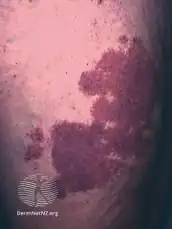

| The back of a hand with prominent port-wine staining | |

Port-wine stain, also known as nevus flammeus, is a birth mark that presents as a dark red or purple area of skin.[1][3] They occur most often on one side of the face or neck;[1][3] though, any part of the body may be involved.[2] They generally have defined borders and over time may become darker and thicken.[2] Complications may include glaucoma.[2]

They generally presents as a dark red or purple area of skin at birth.[1][3] They occur most often on one side of the face or neck;[1][3] though, any part of the body may be involved.[2] They generally have defined borders and over time may become darker and thicken.[2] Complications may include glaucoma.[2]